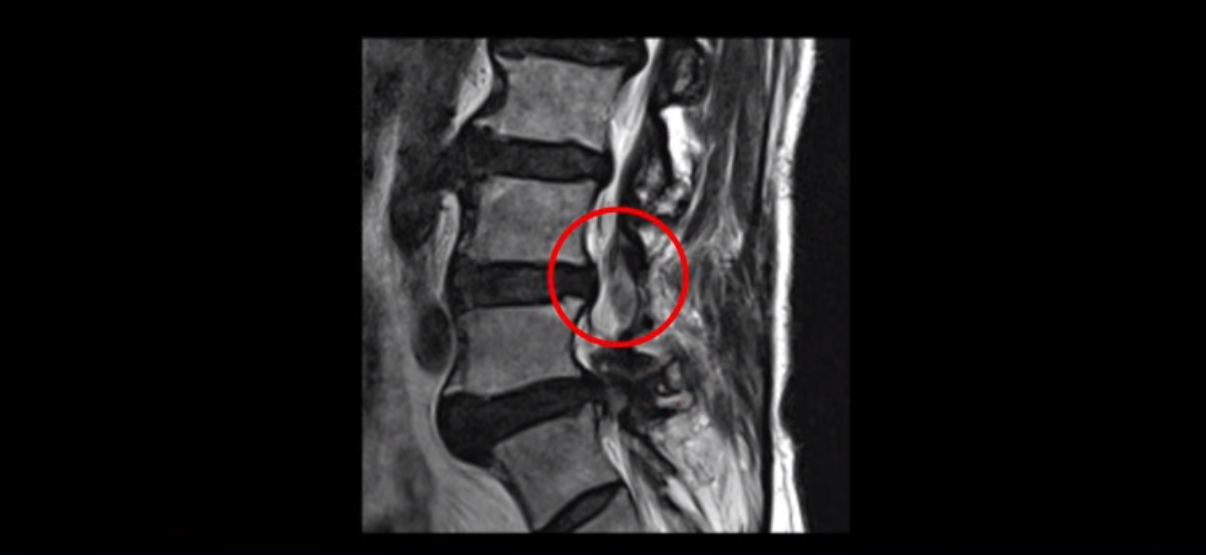

이 환자분은 협착증 수술을 두 번 받은 뒤에 또 다시 다리 방사통이 심해지고 발목 마비 증상(풋드랍)이 생겨서 이번에는 유합술을 권유받은 환자분입니다. 먼저 MRI를 보고 설명해 드린 후 이런 환자분의 방사통과 발목의 마비와 힘 빠짐이 어떻게 수술 없이도 좋아질 수 있는지 그리고 치료는 어떻게 하는지 자세히 설명드리겠습니다.

이분은 허리 다섯 마디 중 4번 5번, 5번 1번에 감압술로 눌린 신경을 풀어주는 수술을 받았습니다.

단면으로 보면 왼쪽 후궁을 제거한 흔적이 보입니다.

5번 1번도 왼쪽 후궁을 열고 수술 받았습니다.

하지만 중심성 협착은 여전히 심한 상태입니다.

이분은 오른쪽, 왼쪽 다리에 모두 방사통이 심하고 왼쪽 다리에 마비 증상, 즉 풋드랍(족하수) 증상이 있습니다. 왼쪽 신경 가지가 빠져나가는 추간공을 보면 두 마디가 좁아져 있습니다.

이런 신경 구멍이 좁아져 있는 걸 협착이라고 합니다.

이미 앞선 두 번의 수술로 뼈와 인대 등을 일부 제거해서 안정성이 떨어진 상태에서 추가로 수술하려니까 척추가 너무 불안정해져 무너질 게 걱정되니까 이번에는 나사 박는 유합술을 권유 받은 겁니다. 이런 환자분들의 방사통과 마비 증상이 어떻게 수술 없이 좋아질 수 있을까요? 치료는 어떻게 하는 걸까요?